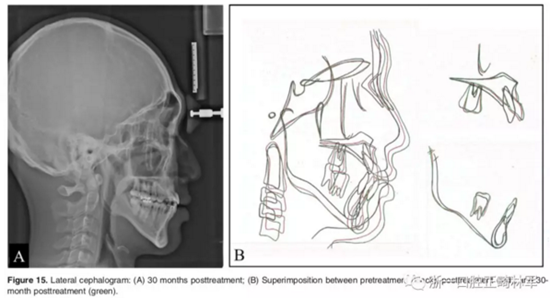

影像學:頭顱側位片示:矢狀向和垂直向骨骼發(fā)生變化(ANB角,3°;SN-MP,51°);上頜切牙略前傾(U1-SN,106°),與下頜切牙一致(IMPA,75°);病人的面部輪廓得以保持。全景片示:由于牙齒萌出,上前牙區(qū)垂直向牙槽骨水平增加;雖然前牙牙根較彎曲,但其平行度仍可,且無明顯的牙根吸收。CBCT示:前牙唇側骨質(zhì)連續(xù)性改善,牙根唇側支持組織變好,牙槽骨高度、厚度均有增加,但轉(zhuǎn)矩的改變一定程度上導致了局部應力的增大。

2年隨訪:咬合關系保持穩(wěn)定,無明顯復發(fā),下頜有一定晚期生長趨勢;前牙牙齦外形、牙冠高度無明顯變化;唇側牙槽骨高度、厚度均保持良好。